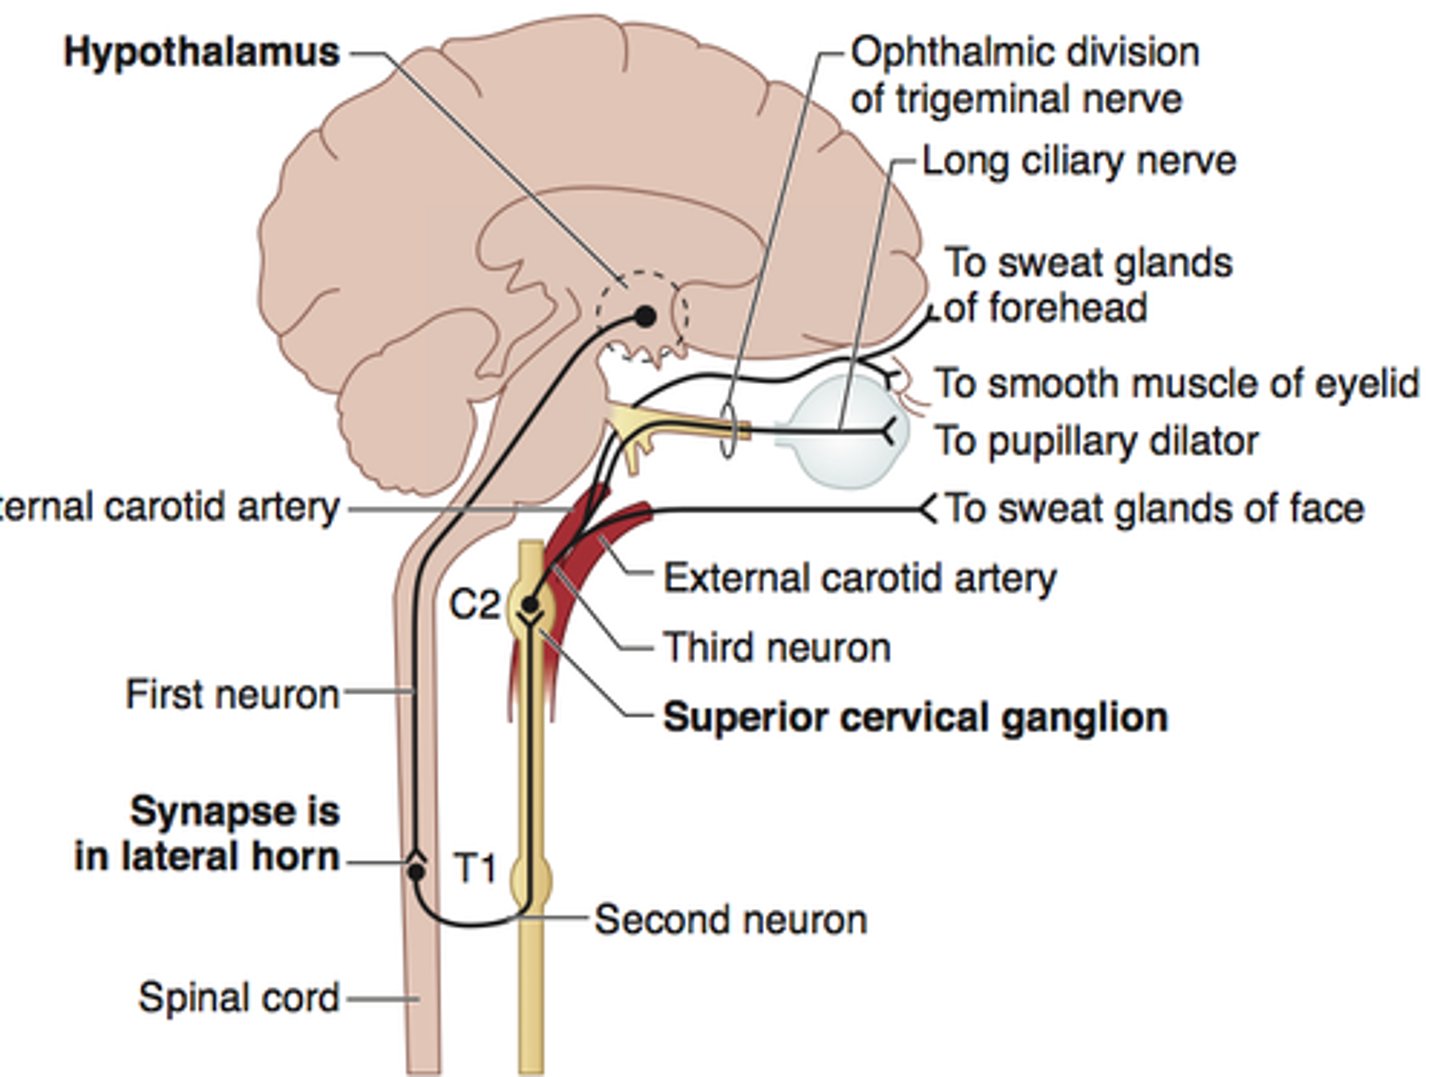

Ptosis, miosis, anhidrosis (no sweating)

Horner syndrome (sympathetic chain lesion)